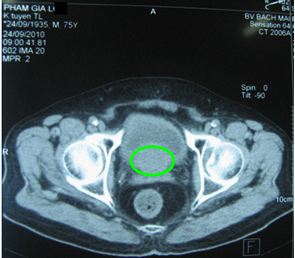

Ở Việt Nam, Mai Trọng Khoa và cộng sự lần đầu tiên thành công trong việc ứng dụng kỹ thuật PET/CT mô phỏng lập kế hoạch xạ trị điều biến liều (IMRT) cho bệnh nhân UTTTL. Ngoài ra PET/CT cũng được sử dụng để đánh giá hiệu quả điều trị cho các bệnh nhân ung thư tuyến tiền liệt (hình 2).

Hình 2. Hình ảnh CT và PET/CT trước điều trị của một bệnh nhân nam 75 tuổi được chụp tại Trung tâm Y học hạt nhân và ung bướu-Bệnh viện Bạch Mai. Bệnh nhân bị đi tiểu ra máu, tiểu khó. Mô bệnh học sau sinh thiết là: ung thư biểu mô tuyến. PSA: 145 ng/ml. Tuyến tiền liệt to: 6 x 4,9 x 5,1 cm, nhu mô không đồng nhất, tăng hấp thu FDG không đồng đều, max SUV=4,98. Có chỉ định xạ trị điều biến liều (IMRT): 6 trường chiếu, 45 segments, đạt tổng liều 74 Gy vào u.

Hình 3. Hình ảnh trước và sau điều trị ung thư tuyến tiền liệt